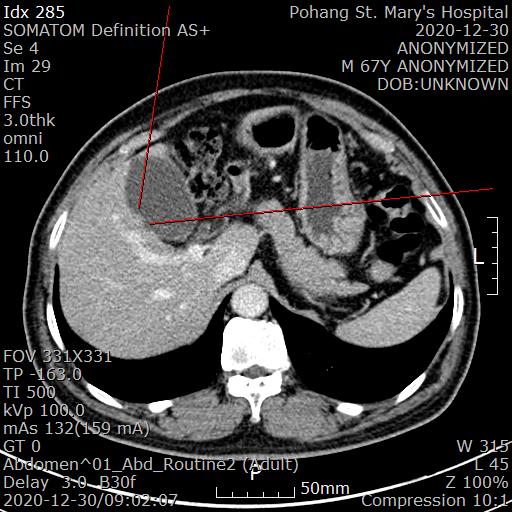

복부 CT를 시행했습니다.

[복부 CT 판독]

A 1 cm flat GB polyp (Se4 #29)

---> Recommendation : Cholecystectomy to rule out GB cancer

담낭에 flat(평평한)한 용종이 있으며 담낭암(GB cancer)의 가능성이 있어 담낭절제를 시행하라는 소견입니다.